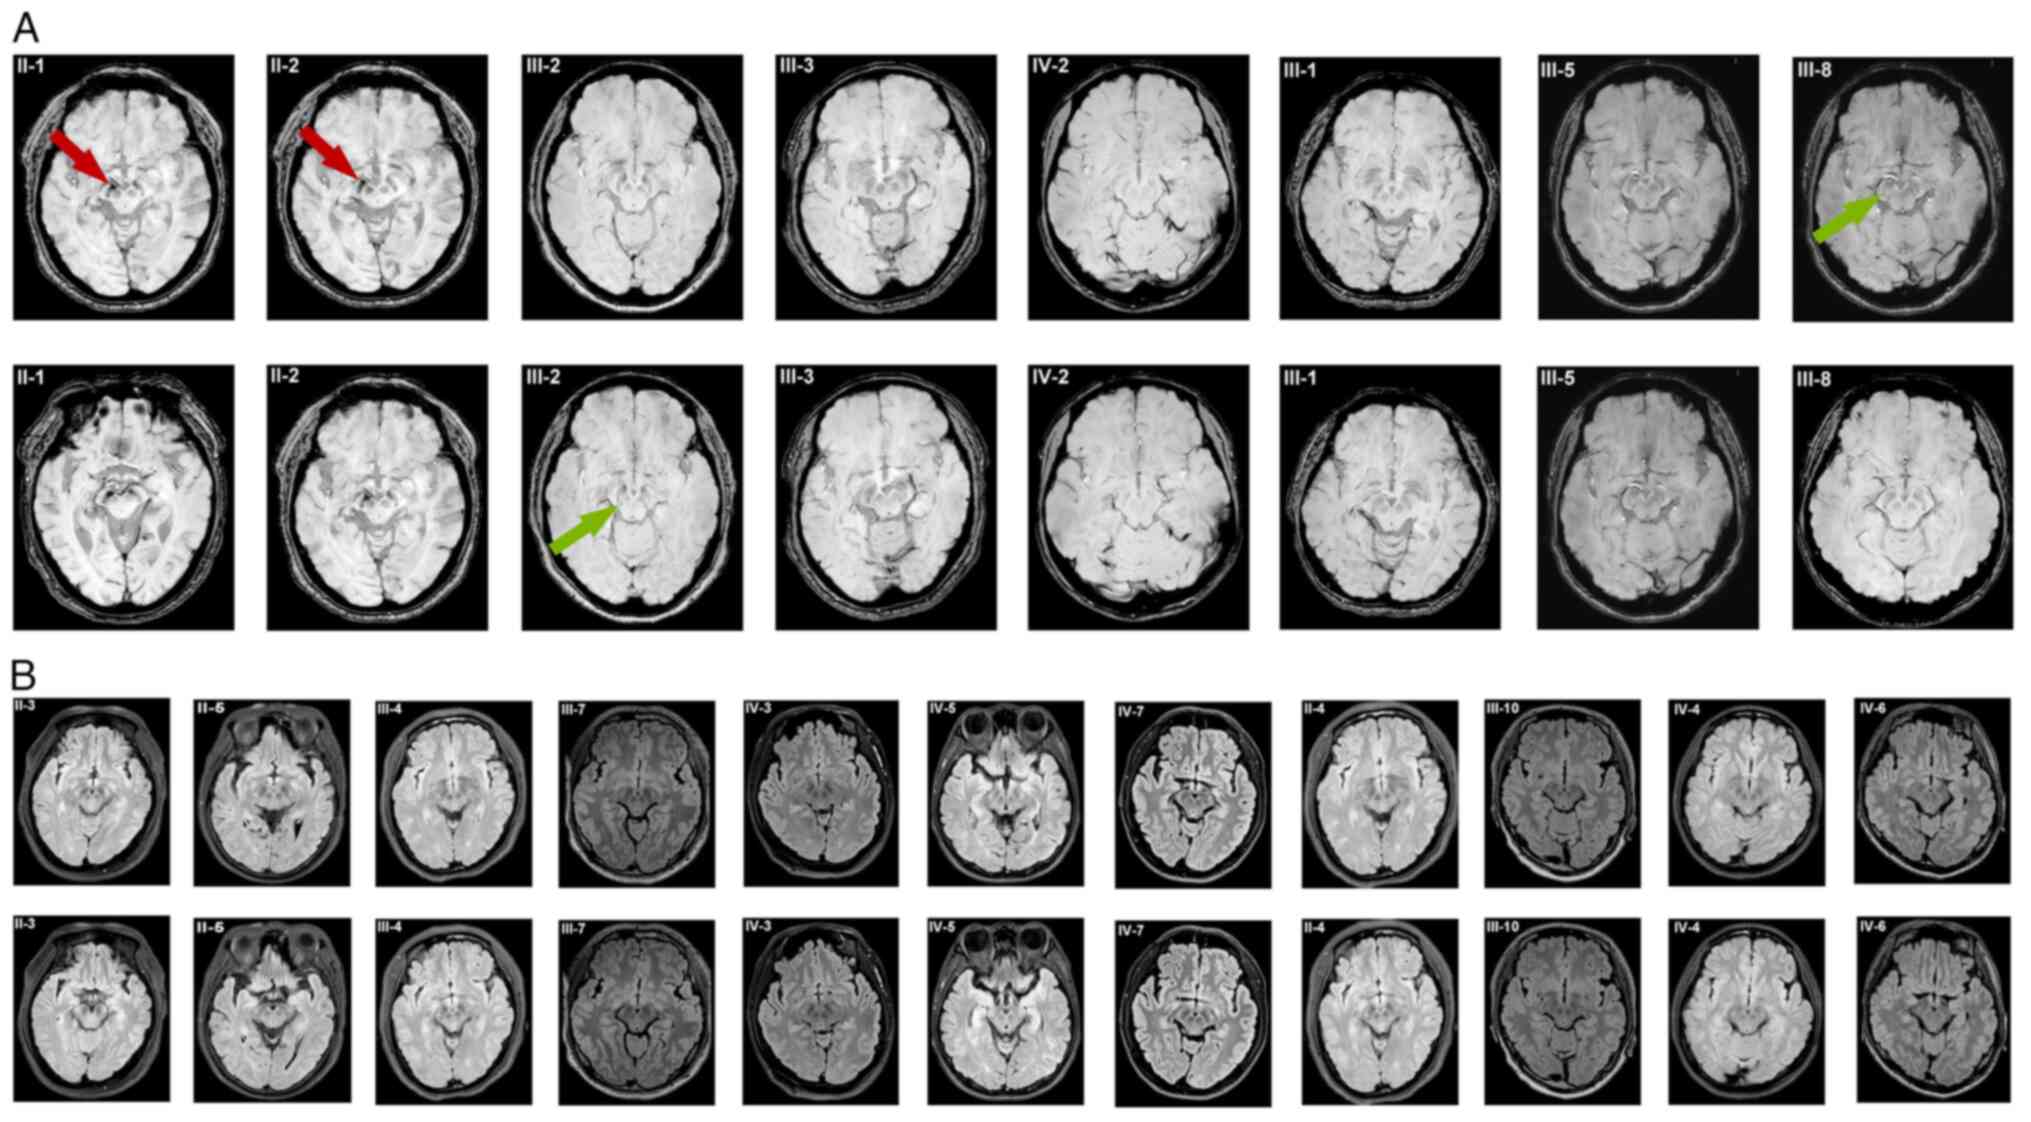

Eukaryotic translation initiation factor EIF4G1 p.Ser637Cys mutation in a family with Parkinson's disease with antecedent essential tremor

Essential tremor (ET) and Parkinson's disease (PD) are common chronic movement disorders that can cause a substantial degree of disability. However, the etiology underlying these two conditions remains poorly understood. In the present study, Whole‑exome sequencing of peripheral blood samples from the proband and Sanger sequencing of the other 18 family members, and pedigree analysis of four generations of 29 individuals with both ET and PD in a nonconsanguineous Chinese family were performed. Specifically, family members who had available medical information, including historical documentation and physical examination records, were included. A novel c.1909A>T (p.Ser637Cys) missense mutation was identified in the eukaryotic translation initiation factor 4γ1 (EIF4G1) gene as the candidate likely responsible for both conditions. In total, 9 family members exhibited tremor of the bilateral upper limbs and/or head starting from ages of ≥40 years, 3 of whom began showing evidence of PD in their 70s. Eukaryotic initiation factor 4 (eIF4)G1, a component of the translation initiation complex eIF4F, serves as a scaffold protein that interacts with many initiation factors and then binds to the 40S ribosomal subunit. The EIF4G1 (p.Ser637Cys) might  inhibit the recruitment of the mRNA to the ribosome. In conclusion, the results from the present study suggested that EIF4G1 may be responsible for the hereditary PD with ‘antecedent ET’ reported in the family assessed.

Figure 1

Figure 2

Figure 3